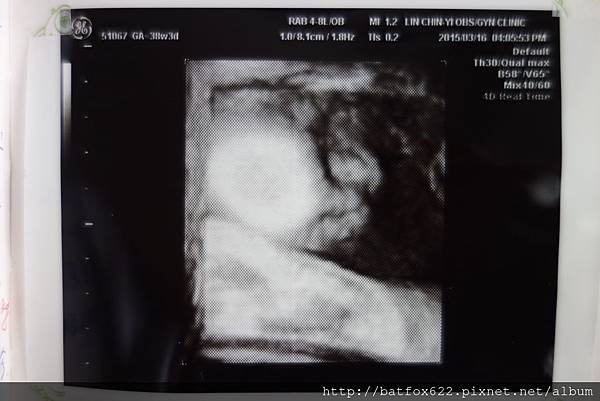

這禮拜,寶寶已經滿38W,我隨時都在等待產兆的出現

哇~來到媽媽手冊中的第十次產檢囉~

也預計是最後一次產檢啦,因為下周就跟醫生約好剖腹的時間啦~

這次比較不一樣...衛教結束後先去待產室監測寶寶心跳(胎動)